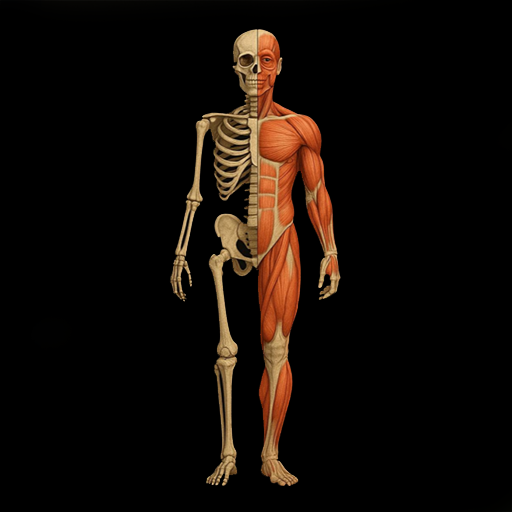

2. Почему именно опорно-двигательная система?

Опорно-двигательная система — это каркас вашей жизни.

📍 Кости дают прочность.

📍 Суставы — гибкость.

📍 Мышцы — движение.

Если каркас ломается — рушится всё. От позвоночника до сердца, от суставов до дыхания. Восстановление этой системы = возвращение себе жизни в движении.